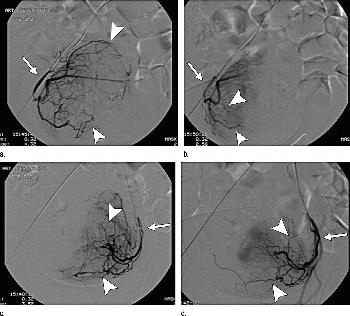

Figure 1. Digital subtraction angiography images show partial UFE. (a) Catheter is placed into right internal iliac artery with catheter tip in initial part of uterine artery (arrow); hypervascularization of fibroid is shown (arrowheads). (b) After partial UFE, uterine artery (arrow) is patent and there is some reduction of fibroid vessels, although some vessels are still shown (arrowheads). (c) Catheter is placed into left internal iliac artery with catheter tip in initial part of uterine artery (arrow); hypervascularization of fibroid is shown (arrowheads). (d) After partial UFE, uterine artery (arrow) is patent and there is some reduction of small fibroid vessels, although some vessels are still shown (arrowheads).